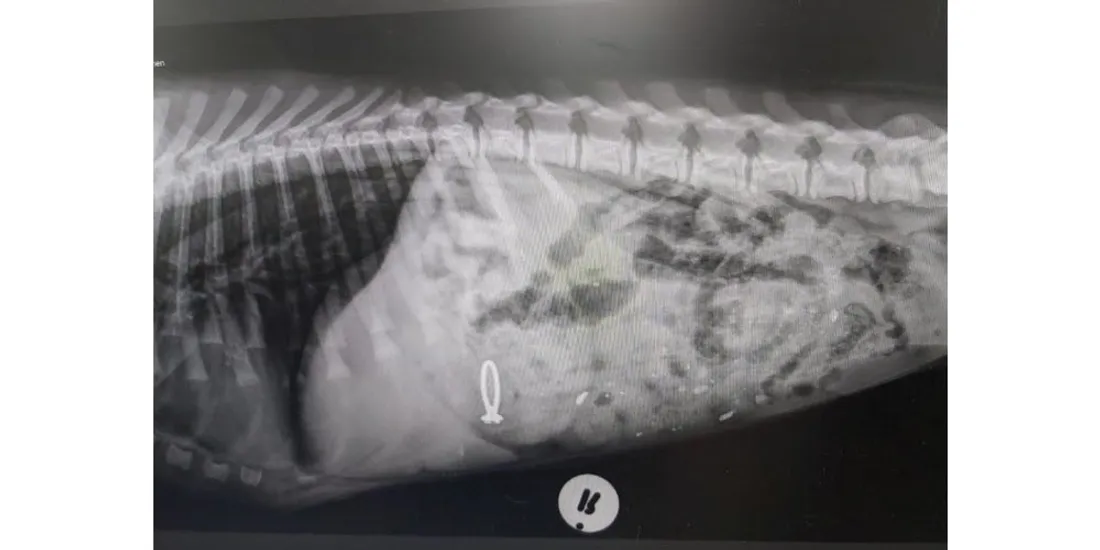

Il fait la tête et pour cause ! Ce que ce chien a avalé n’est pas tellement digeste. Photographié par un vétérinaire ce chien Pepper vient d’avaler la bague de fiançailles de sa maîtresse. "Mon nom est Pepper. Vous avez l’impression que j’ai mal au cœur ? Et oui, car le vétérinaire vient de me donner un vomitif. Il n’est pas méchant, j’ai juste avalé la bague de fiançailles de ma maman !", a commenté l’hôpital vétérinaire avec la photo.

Et en effet sur la radiographie on retrouve bien le fameux anneau surmonté d’un diamant perdu dans l’estomac du canidé. Heureusement, grâce à un médicament sa propriétaire a pu récupérer sa bague…